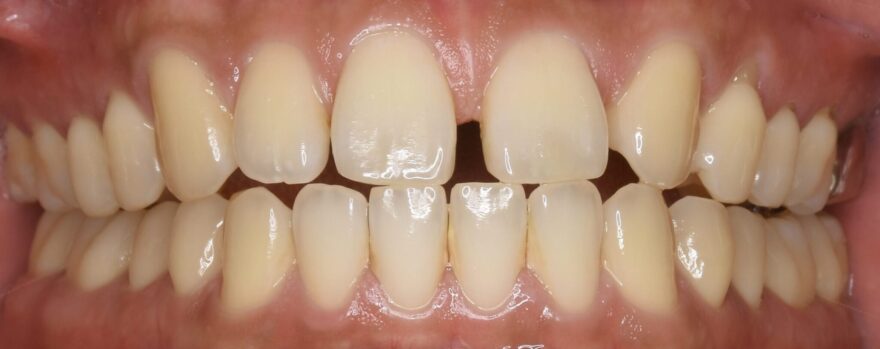

After

全体的な噛み合わせが狂ってしまい、どこで噛んでいいか分からない状態でした。

8本のインプラント治療と16本のセラミック治療で、しっかり上下の歯が噛み合う状態にしました。

奥歯インプラント8本→3,520,000円(税込)

《1本あたり440,000円(税込)》

前歯プレミアムセラミック12本→1,980,000円

《1本あたり165,000円(税込)》

奥歯プレミアムセラミック10本→1,430,000円

《1本あたり143,000円(税込)》

ファイバーコア5本→110,000円(税込)

《1本あたり22,000円(税込)》

前歯精密根管治療2本→220,000円

《1本あたり110,000円(税込)》

咬合再構成(全ての仮歯代とデジタルデザイン含む)24本→792,000円

《1本あたり33,000円(税込)》

総額 8,052,000円(税込)